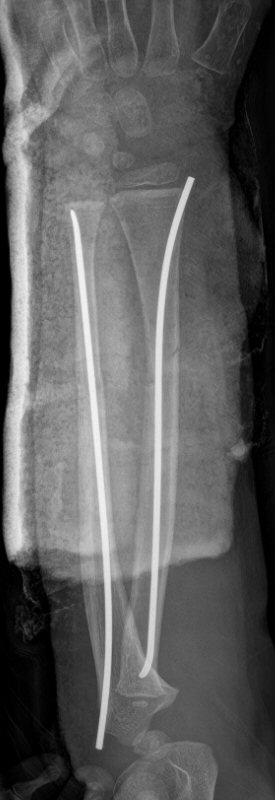

Exempel på rötngenbilder vid TEN-spikning:

Frontalbilder före och efter operation, resp. sidobilder före och efter operation med TEN-spikning i radius och ulna